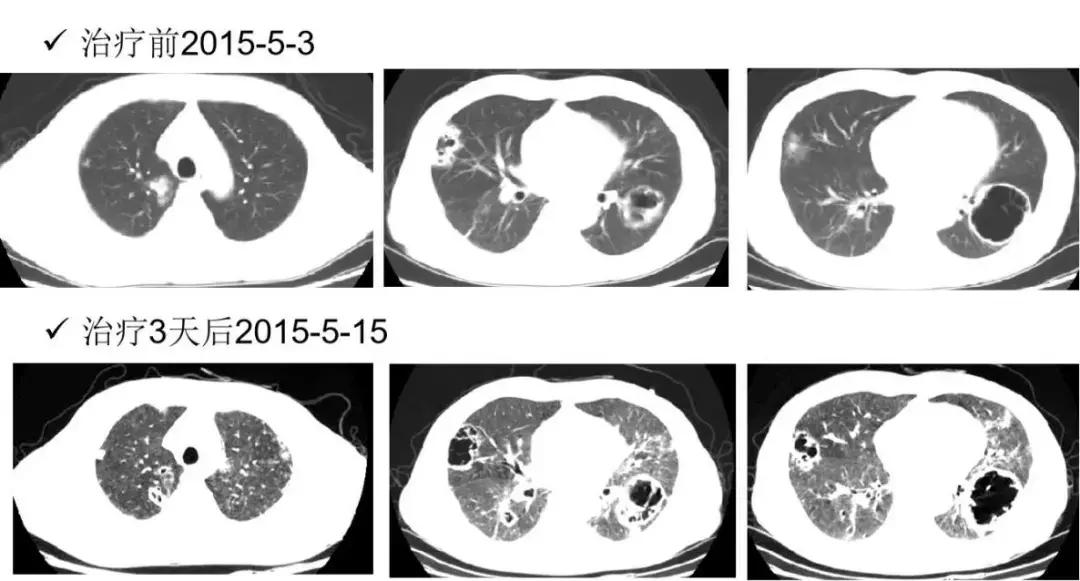

双药联合抗奴卡菌治疗2015-5-13(入院后第7天):复方磺胺甲噁唑 1.44g(磺胺含量1.2g) q6h + 亚胺培南西司他丁 1g q8h;同时经肾内科会诊后调整免疫抑制用药: 2015-5-13(入院后第7天)停用他克莫司,甲泼尼龙改为32mg qd,并每3~5日减4mg,至20mg qd。

2015-5-15(入院后第9天)抗奴卡菌治疗第3天,患者诉右侧胸痛较前有所缓解,但感呼吸困难,咳嗽、咳痰好转不明显,查体:双肺散在哮鸣音,血气分析(吸氧2L/min):pH 7.48,PaO2 60.3mmHg,PaCO2 28.8mmHg,HCO3- 21.7mmol/L。

2015-5-16(入院后第10天)抗奴卡菌治疗第4天,继续复方磺胺甲噁唑 1.44g q6h+亚胺培南西司他丁 1g q8h抗奴卡菌,并加用伏立康唑 200mg q12h抗真菌治疗(首剂400mg)。